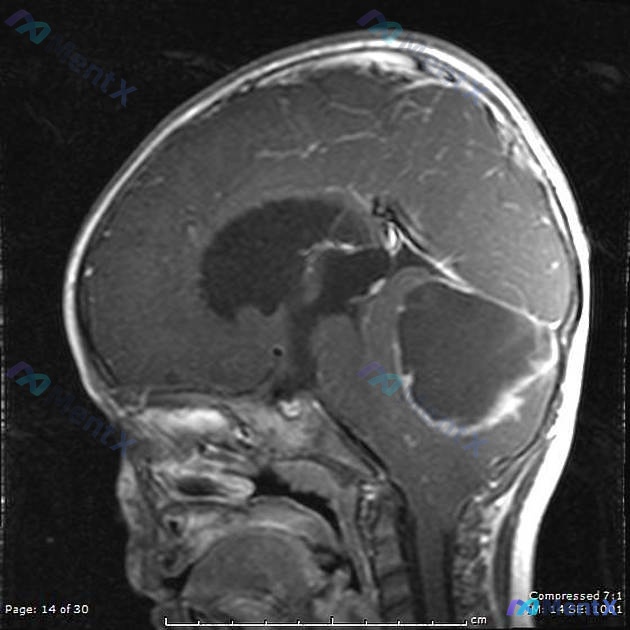

整理了一个很有意思的儿童后颅窝病例,感觉在「不要被锚定思维带偏」这点上很有启发,分享一下完整思路。 --- 病例核心信息 患儿:5岁男孩,无特殊病史,发育达标(能说完整句子、数到20、单脚跳)。 主诉:头痛1个月,伴左臂偶尔「笨拙」,近1周呕吐十多次。 查体: - 神清配合,瞳孔等大等圆对光好,颅神...

整理到一个儿童后颅窝占位的病例资料,大家可以结合信息讨论一下。 患儿8岁,因「反复头痛、呕吐伴步态不稳1个月」就诊。查体发现:视盘水肿,指鼻试验阳性,跟膝胫试验不稳。 MRI表现:小脑蚓部可见3cm×3cm实性占位,T1像呈低信号,T2像呈稍高信号,增强扫描明显强化,同时伴有梗阻性脑积水。 这类表现...